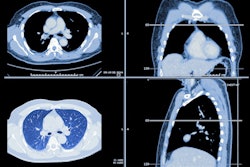

But reducing radiation exposure tends to lead to more image noise. Gorenstein and colleagues conducted a study that applied the adaptive statistical iterative reconstruction AI algorithm to a set of ultralow-dose CT studies. The study included 119 patients who underwent a low-dose CT scan and an ultralow-dose CT scan; two readers compared images that were processed with the AI algorithm to those that were not.

Overall, the AI algorithm reduced ultralow-dose CT radiation dose by 76% compared with regular LDCT, and there was no statistically significant difference between negative and actionable Lung-RADS categories between the two techniques.

| Comparison of ultralow-dose CT to denoised ultralow-dose CT for lung cancer screening | |||

| Measure | Ultra-LDCT | AI denoised ultra-LDCT | Percent difference |

| Standard deviation (the lower the SD, the lower the image noise) | 32.3 HU | 25 HU | -22.3% |

| Signal-to-noise ratio (the higher the ratio, the better the signal quality) | 33.7 | 43.4 | 28.7% |

| Coronary artery calcifications (CACs) identified in patient cohort | 62.2% | 74% | 19% |

The group also found that interreader agreement for assessing CAC was almost perfect: 0.9 for LDCT, 0.9 for denoised ultra-LDCT, and 0.81 for ultra-LDCT.